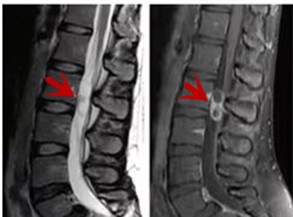

MRI利于磁場和射頻脈沖使體內(nèi)的氫原子核發(fā)生磁共振現(xiàn)象而產(chǎn)生的圖像,對軟組織的分辨率很高,對于脊髓、椎間盤、神經(jīng)、血管、韌帶、骨髓、腰部肌肉及周圍軟組織有很好的顯示效果,可以清晰的顯示腰椎間盤突出對硬膜囊、神經(jīng)根壓迫程度,以及骨折是陳舊還是新鮮,同時在脊髓病變(如脊髓損傷、髓內(nèi)出血或腫瘤)、椎管內(nèi)膿腫/血腫、椎旁肌肉軟組織病變等方面也具有優(yōu)勢,但是檢查時間較長,部分患者可能因體內(nèi)金屬植入物(如心臟起搏器、人工耳蝸等)而無法進行檢查。

箭頭提示腰椎管內(nèi)腫瘤

紅色箭頭提示新鮮骨折,黃色箭頭提示陳舊性骨折